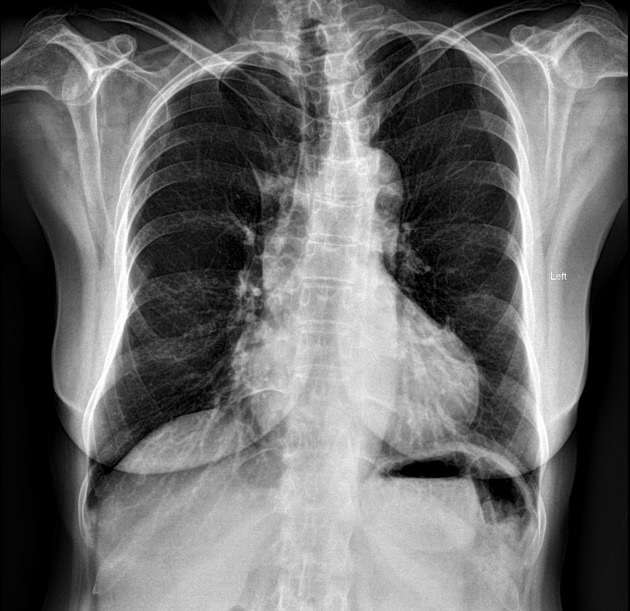

Dans coartation ismique

aortique , cette lesion due une dilatation des

artere collateral en amont et ses branches ce sont

arteres intercostales droit et gauche . Ce qui

entraine de image de encroche costale au bord

inferieure des cotes |

Image radiologique du cliche

analogue pulmonaire PA d'une encroche costale de

bord inferieure des côtes droit et gauche ( flèche

rouge ) d'une coartation ismique aortique . |

Image radiologique PA cliche

de face pulmonaire d'une cartation istmique aortique

avec image de dilatation de aort ascendante ,

dilatation post stenotique de aort descendante ,

double courbe de bouton aortique et image de

encrhoche costale des cotes droites ( flèche rouge ) |

|

Même cas en schematisee , on

peut en vue net image d'encrohe costale des côtes

droites ( en flèche ) et image en double bouton du

cros aortique |